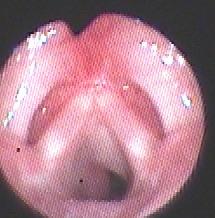

1.2诊断标准与方法对于可疑SGH患儿均需行纤维喉镜检查,声门下单侧或双侧局部隆起,表面光滑、暗红色,阻塞声门下气道,则高度怀疑SGH(图1)。颈部增强CT见声门下局部软组织增厚,气道变窄,增强扫描强化明显(图2a,b,c),诊断明确后给药。

a.治疗前见声门下左侧壁红色、光滑隆起。

b:口服普萘洛尔治疗1年后复查喉镜,声门下血管瘤消失。